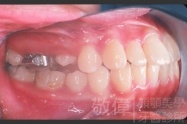

變臉矯正,原來戽斗妹跟大歪臉變成自信正妹

經由本院3D數影X光影像儀分析、與3D齒顎顏矯正技術,再配合口腔顎面正顎專科醫師施以正顎手術治療,雙方共同合作,使患者臉部外觀有很好的改善,大歪變小歪,產生了天南地北的大改變,她的人生也整個變得不一樣。

因為矯正與正顎手術的配合,使「戽斗妹」變成了「陽光正妹」,完全的改變了她的人生,在面對各種場合、與人交際都散發出自信微笑。所以,奉勸家長,如果小朋友有臉顎畸型的問題,應該考慮配合做這種簡單、安全、有效的正顎手術。